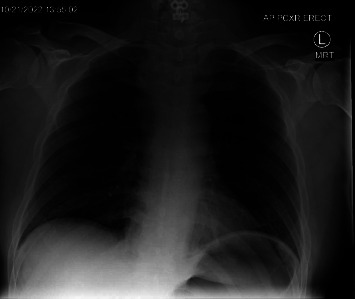

本病例讨论的是一名 47 岁的高加索男性,既往病史包括血脂异常、胃食管反流病、既往颈椎手术和焦虑症,在进行 C5-6 颈椎融合术后出现颈部血肿。医生紧急进行了颈部探查并清除了血肿,恢复了通气。患者被转入重症监护室,术后第 5 天拔管,伤口稳定,无残留出血。三周后复诊时,患者情况良好,胸片显示无渗出或血肿。本报告阐明了颈椎手术后颈部血肿并发症的急性临床症状及其与潜在病因的相关性、后续处理和结果所带来的挑战。

This case study discusses a 47-year-old Caucasian male with a past medical history of dyslipidemia, gastroesophageal reflux disease, previous cervical spine surgery, and anxiety who developed a neck hematoma postrevision of a C5-6 cervical spine fusion. Emergent neck exploration and evacuation of the hematoma were performed, and ventilation was restored. The patient was transferred to the intensive care unit and extubated on postoperative day 5 with a stable wound and no residual bleeding. At the 3-week follow-up appointment, the patient was noted to be doing well, with a chest radiograph showing no effusion or hematoma. This report elucidates the challenges posed by acute clinical symptoms and their correlation with the underlying cause, as well as the subsequent management and outcomes of a neck hematoma complication following cervical spine surgery.